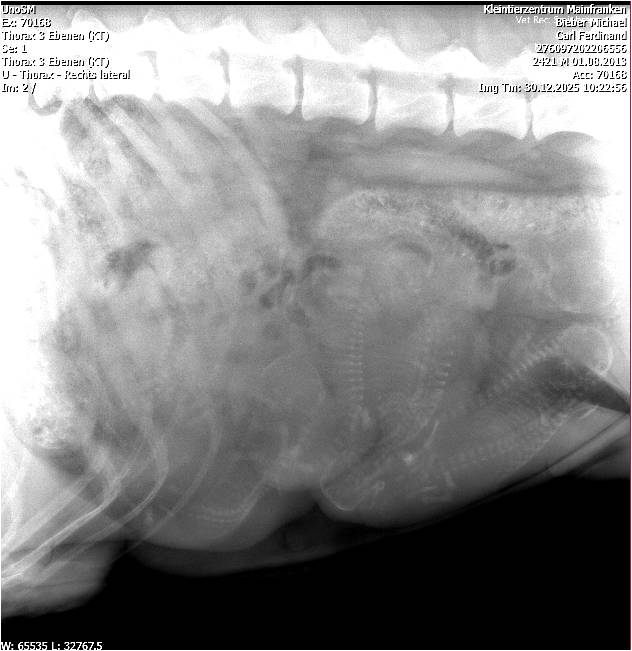

Tag 57 Röntgen

veröffentlicht Dezember 31, 2025 um Tag 57 Röntgen.